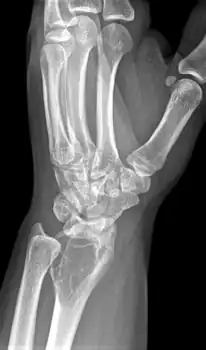

X-ray of a giant-cell bone tumor in the head of the fourth metacarpal of the left hand

On X-ray, giant-cell tumors (GCTs) are lytic/lucent lesions that have an epiphyseal location and grow to the articular surface of the involved bone.[11] Radiologically the tumors may show characteristic 'soap bubble' appearance.[12] They are distinguishable from other bony tumors in that GCTs usually have a nonsclerotic and sharply defined border. About 5% of giant-cell tumors metastasize, usually to a lung, which may be benign metastasis,[13] when the diagnosis of giant-cell tumor is suspected, a chest X-ray or computed tomography may be needed. MRI can be used to assess intramedullary and soft tissue extension.